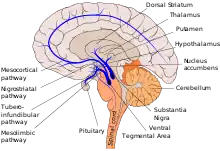

Five major pathways in the brain connect other brain areas to the basal ganglia. These are known as the motor, oculomotor, associative, limbic, and orbitofrontal circuits. Names indicate the main projection area of each circuit.[79] All are affected in PD, and their disruption causes movement-, attention- and learning-related symptoms of the disease.[79] Scientifically, the motor circuit has been examined the most intensively.[79]

Since 1980, a particular conceptual model of the motor circuit and its alteration with PD has been of influence although some limitations have been pointed out which have led to modifications.[79] In this model, the basal ganglia normally exert a constant inhibitory influence on a wide range of motor systems, preventing them from becoming active at inappropriate times. When a decision is made to perform a particular action, inhibition is reduced for the required motor system, thereby releasing it for activation. Dopamine acts to facilitate this release of inhibition, so high levels of dopamine function tend to promote motor activity, while low levels of dopamine function, such as occur in PD, demand greater exertions of effort for any given movement. The result of dopamine depletion is to produce hypokinesia, an overall reduction in motor output.[79] Drugs that are used to treat PD, conversely, may produce excessive dopamine activity, allowing motor systems to be activated at inappropriate times and thereby producing dyskinesias.[79]